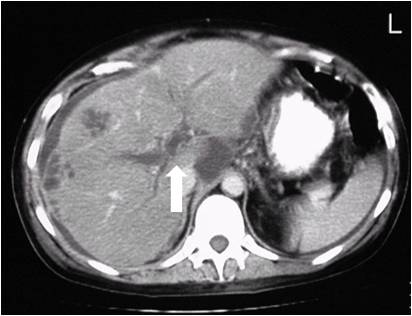

복수